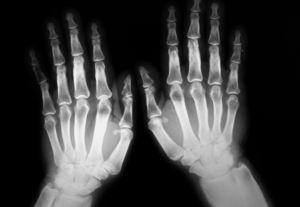

Se le realizó un estudio radiológico (radiografías de cráneo, huesos largos, columna, pelvis, manos y pies) hallándose una hiperostosis en los huesos de los antebrazos, el fémur y la tibia con una periostitis acusada y lesiones de fractura consolidada en la tibia y el peroné izquierdos. En las radiografías de manos se observó una tumefacción de partes blandas, sobre todo en falanges distales, una periostitis y una hiperostosis de los huesos metacarpianos y primeras falanges (fig. 1). En las radiografías de ambos pies también se apreció una hiperostosis de huesos metatarsianos, osteofitos y una esclerosis en el pie derecho.

Figura 1. Hiperostosis y periostitis en huesos metacarpianos y primeras falanges. Tumefacción de partes blandas.